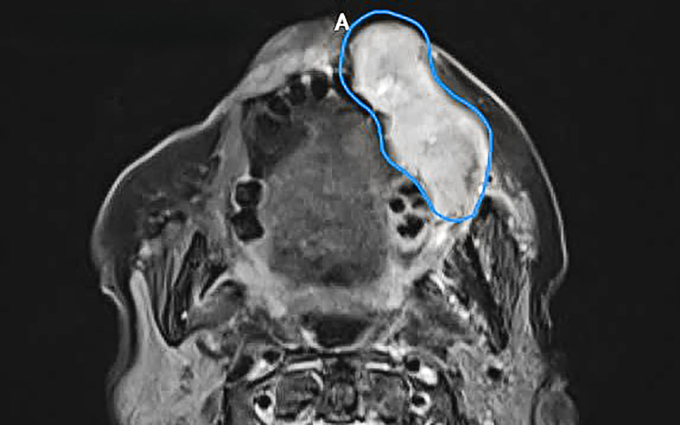

Bà Tình, 80 tuổi, xuất hiện khối u 6 tháng trước rồi tăng dần kích thước khiến mặt bên trái sưng căng đẩy vùng má, môi lồi lõm, lệch hẳn ra ngoài, phía trong miệng lở, rỉ dịch. U lớn nhanh gây đau khiến bà không nói rõ, không thể ăn uống, sụt 5 kg. Kết quả sinh thiết tại Bệnh viện Đa khoa Tâm Anh TP HCM cho thấy khối u dài 7 cm dày 4 cm là ung thư niêm mạc má giai đoạn ba.

Khối u nằm sát da, lồi ra ngoài gây biến dạng khuôn mặt. Do đó, ngoài việc làm mặt nạ cố định có hình dáng đặc biệt ôm theo khối u, bác sĩ còn thiết kế thêm miếng bù liều để đạt hiệu quả chiếu tia tối ưu nhất. Tia xạ mạnh và phát huy tác dụng tốt nhất khi chiếu vào vị trí u dưới bề mặt da khoảng 2-3 cm. Tuy nhiên, ở bệnh nhân này, khối u lan ra vùng môi, miếng bù liều dày khoảng 1 cm làm bằng nhựa cứng, có vai trò như một lớp mô bao phủ phía trên u, giúp tia xạ chiếu trúng đích, giảm tổn thương mô lành dưới u.

Sau 5 lần xạ, người bệnh đáp ứng tốt, khối u giảm kích thước rõ rệt, giảm đau, ăn nhai, nói chuyện dễ dàng hơn. Vùng u lồi ở miệng biến mất, hình dạng khuôn mặt gần như bình thường. Trước những lần xạ tiếp theo, người bệnh được làm lại mặt nạ cố định, miếng bù liều cho ôm sát vùng điều trị.